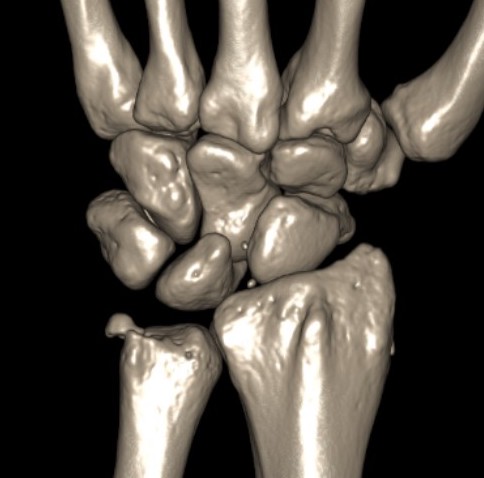

Galeazzi fracture

Galeazzi fracture with DRUJ disruption

Incidence of DRUJ instability after radius ORIF

Rettig et al J Hand Surg Am 2001

- 40 patients with Galeazzi fracture dislocations

- DRUJ instability after radius ORIF

- Type 1: radius fracture < 7.5 cm to articular surface: 55% DRUJ instability

- TYpe II: radius fracture > 7.5 cm to articular surface: 6% DRUJ instability